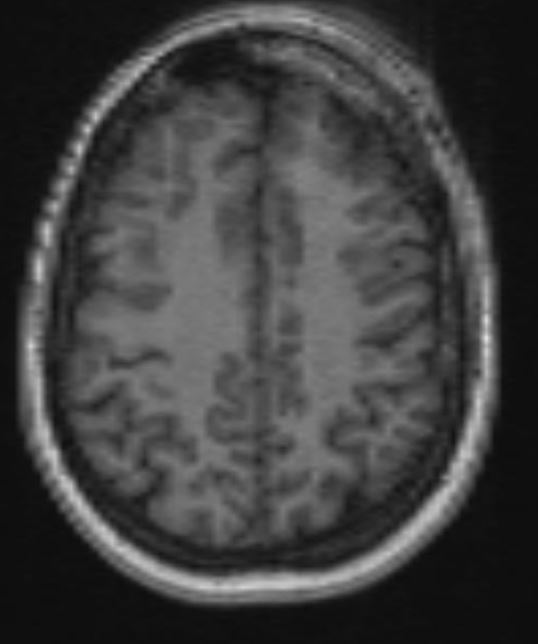

The structural correlates of the above EEG findings appear below. There is enlargement of the left-ventricular system, atrophy of the head, body and tail of the caudate nucleus and the left hemisphere appears modestly smaller in size than the right, most evident on axial sequences. The MRI was done while the patient was quite restless. As you can see from these pictures, the left occipital cortex and the left thalamus do not demonstrate any structural correlate to the asymmetry of alpha rhythms. However, we know from the EEG that the left hemisphere is markedly dysfunctional. Unsurprisingly, on functional MRI scans language is represented in the right hemisphere.